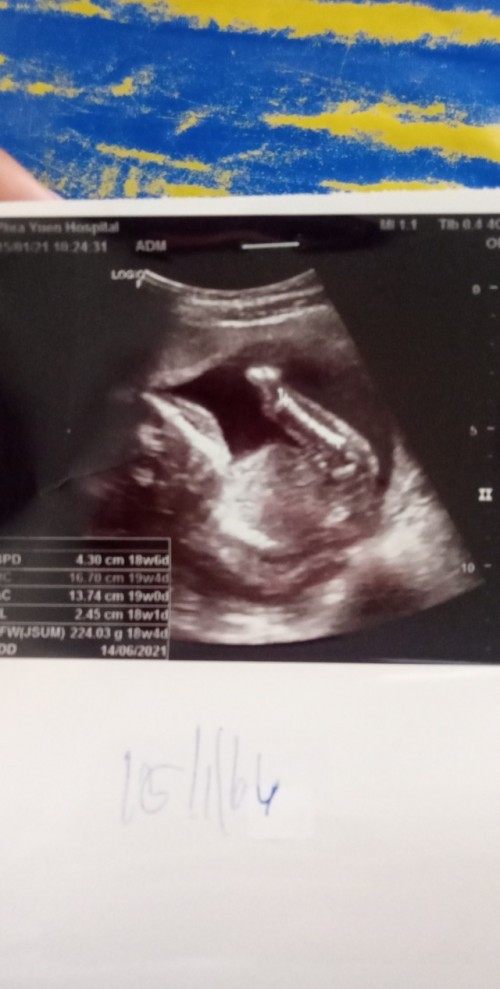

19+6จ้า